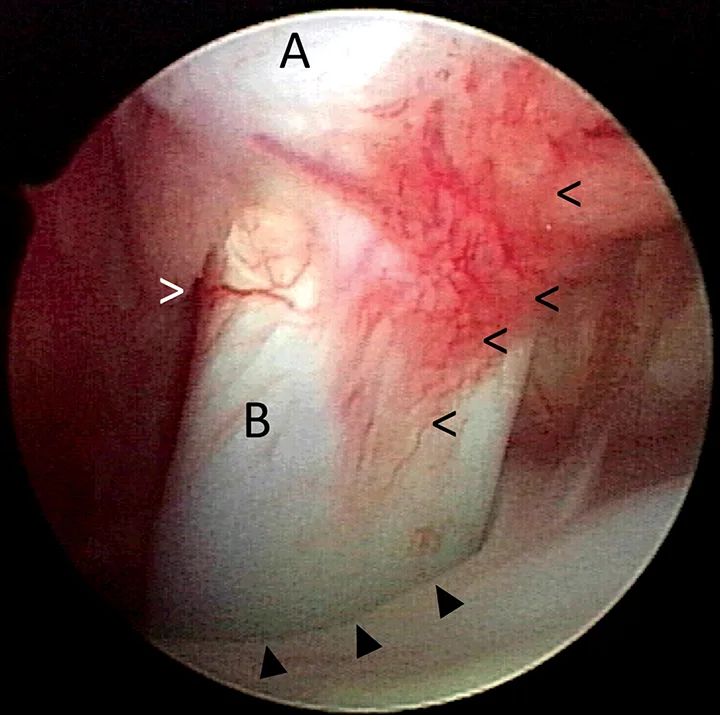

Arthroscopic image of the shoulder joint of a dog with biceps tenosynovitis. The biceps tendon (B) originates on the supraglenoid tuberosity of the scapula (A) and traverses distally through the bicipital groove of the humerus (closed arrowheads). Synovitis and increased vascularity of the tendon sheath are present (open arrowheads).